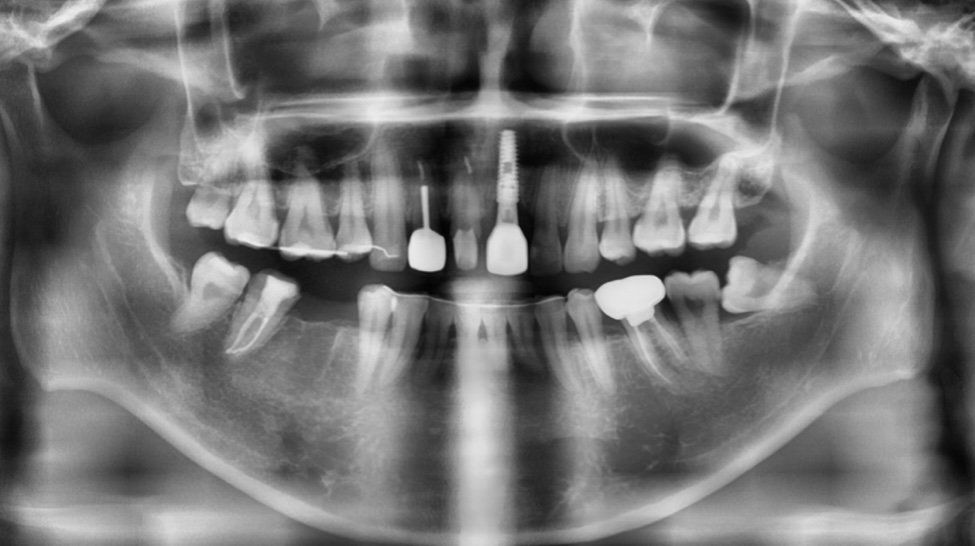

사진 첨부합니다 해당 치아는 임플란트 옆에 앞니입니다

사진상으로는 염증이 그렇게 심한거 같지 않는거 같습니다. 발치하시고 염증을 충분히 긁어내고 임플란트 심어도 크게 문제가 되진 않을것같습니다.

정확히 보기위해선 씨티 사진이 필요합니다.

파노라마만 봐서는 정확히 판단하긴 어렵습니다.

보통 앞니는 심미적인 부위이기 때문에 웬만해서는 발치즉시 식립을 하게되지만, 염증이 너무 심하다면 발치후 기다렸다가 심는게 좋습니다. 감사합니다.